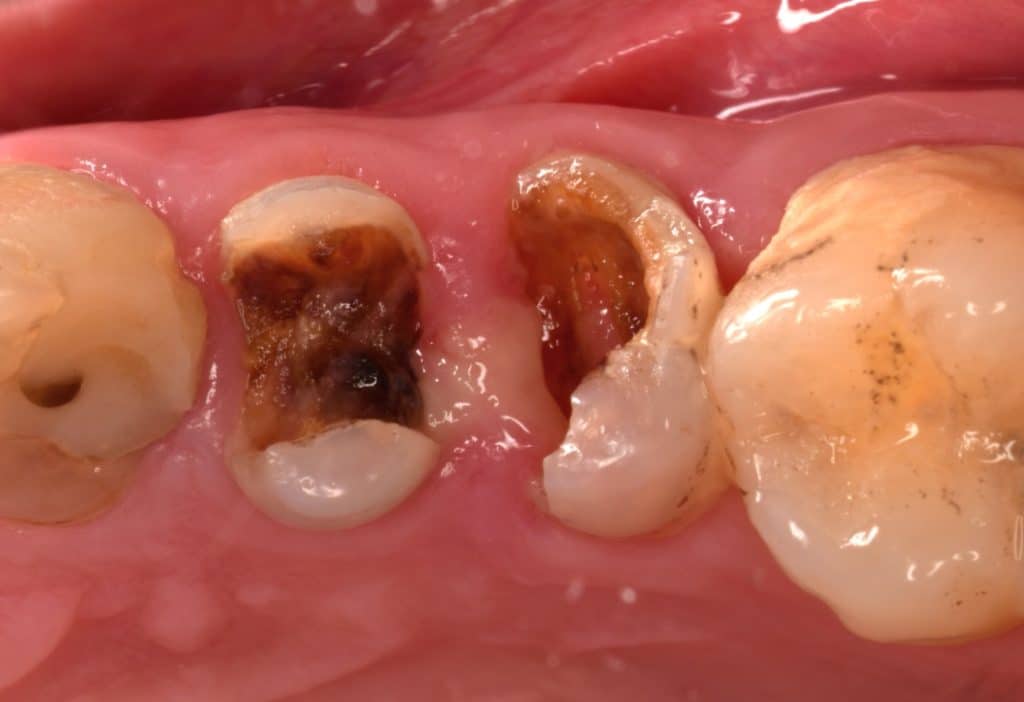

Initial situation showing large carious lesion in the upper premolars

Buccal view showing the extension of the caries